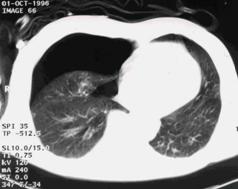

Imagine

CT Imagine CT

Contuzie pulmonara stanga Contuzie pulmonara dreapta

Contuzie pulmonara dreapta.Imagine CT